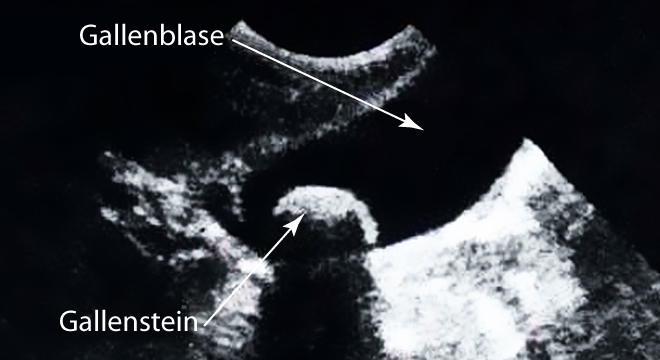

Gallensteine sind, wie der Name bereits vermuten lässt, steinartige Gebilde, die sich in der Gallenblase oder in den Gallengängen unter bestimmten Voraussetzungen bilden können.

• Ultraschall